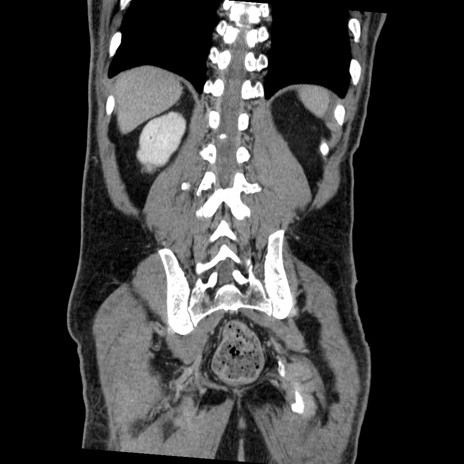

症例22(冠状断像)

【症例】50歳代男性

【主訴】腹痛

【現病歴】AVMからの被殻出血のため回復期リハ病棟入院中。 本日午後3時頃急に下腹部痛が出現した。

【既往歴】AVM、被殻出血、虫垂炎、高血圧

【身体所見】意識晴明、左半身不全麻痺、会話の理解は良好、36.5°C、腹部:膨隆、全体に板状硬、下腹部正中に圧痛点あり、反跳痛-、筋性防御不明、右下腹部にope scar

【データ】WBC 9400、CRP 0.06